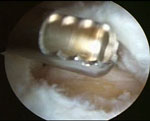

διαμέσου οπτικών ινών. Το αρθρωσκόπιο στο άκρο του φέρει πολύ

μικρού μεγέθους κάμερα η οποία είναι συνδεδεμένη με μια οθόνη

όπου απεικονίζεται το εσωτερικό της άρθρωσης. Με αυτή τη μέθοδο